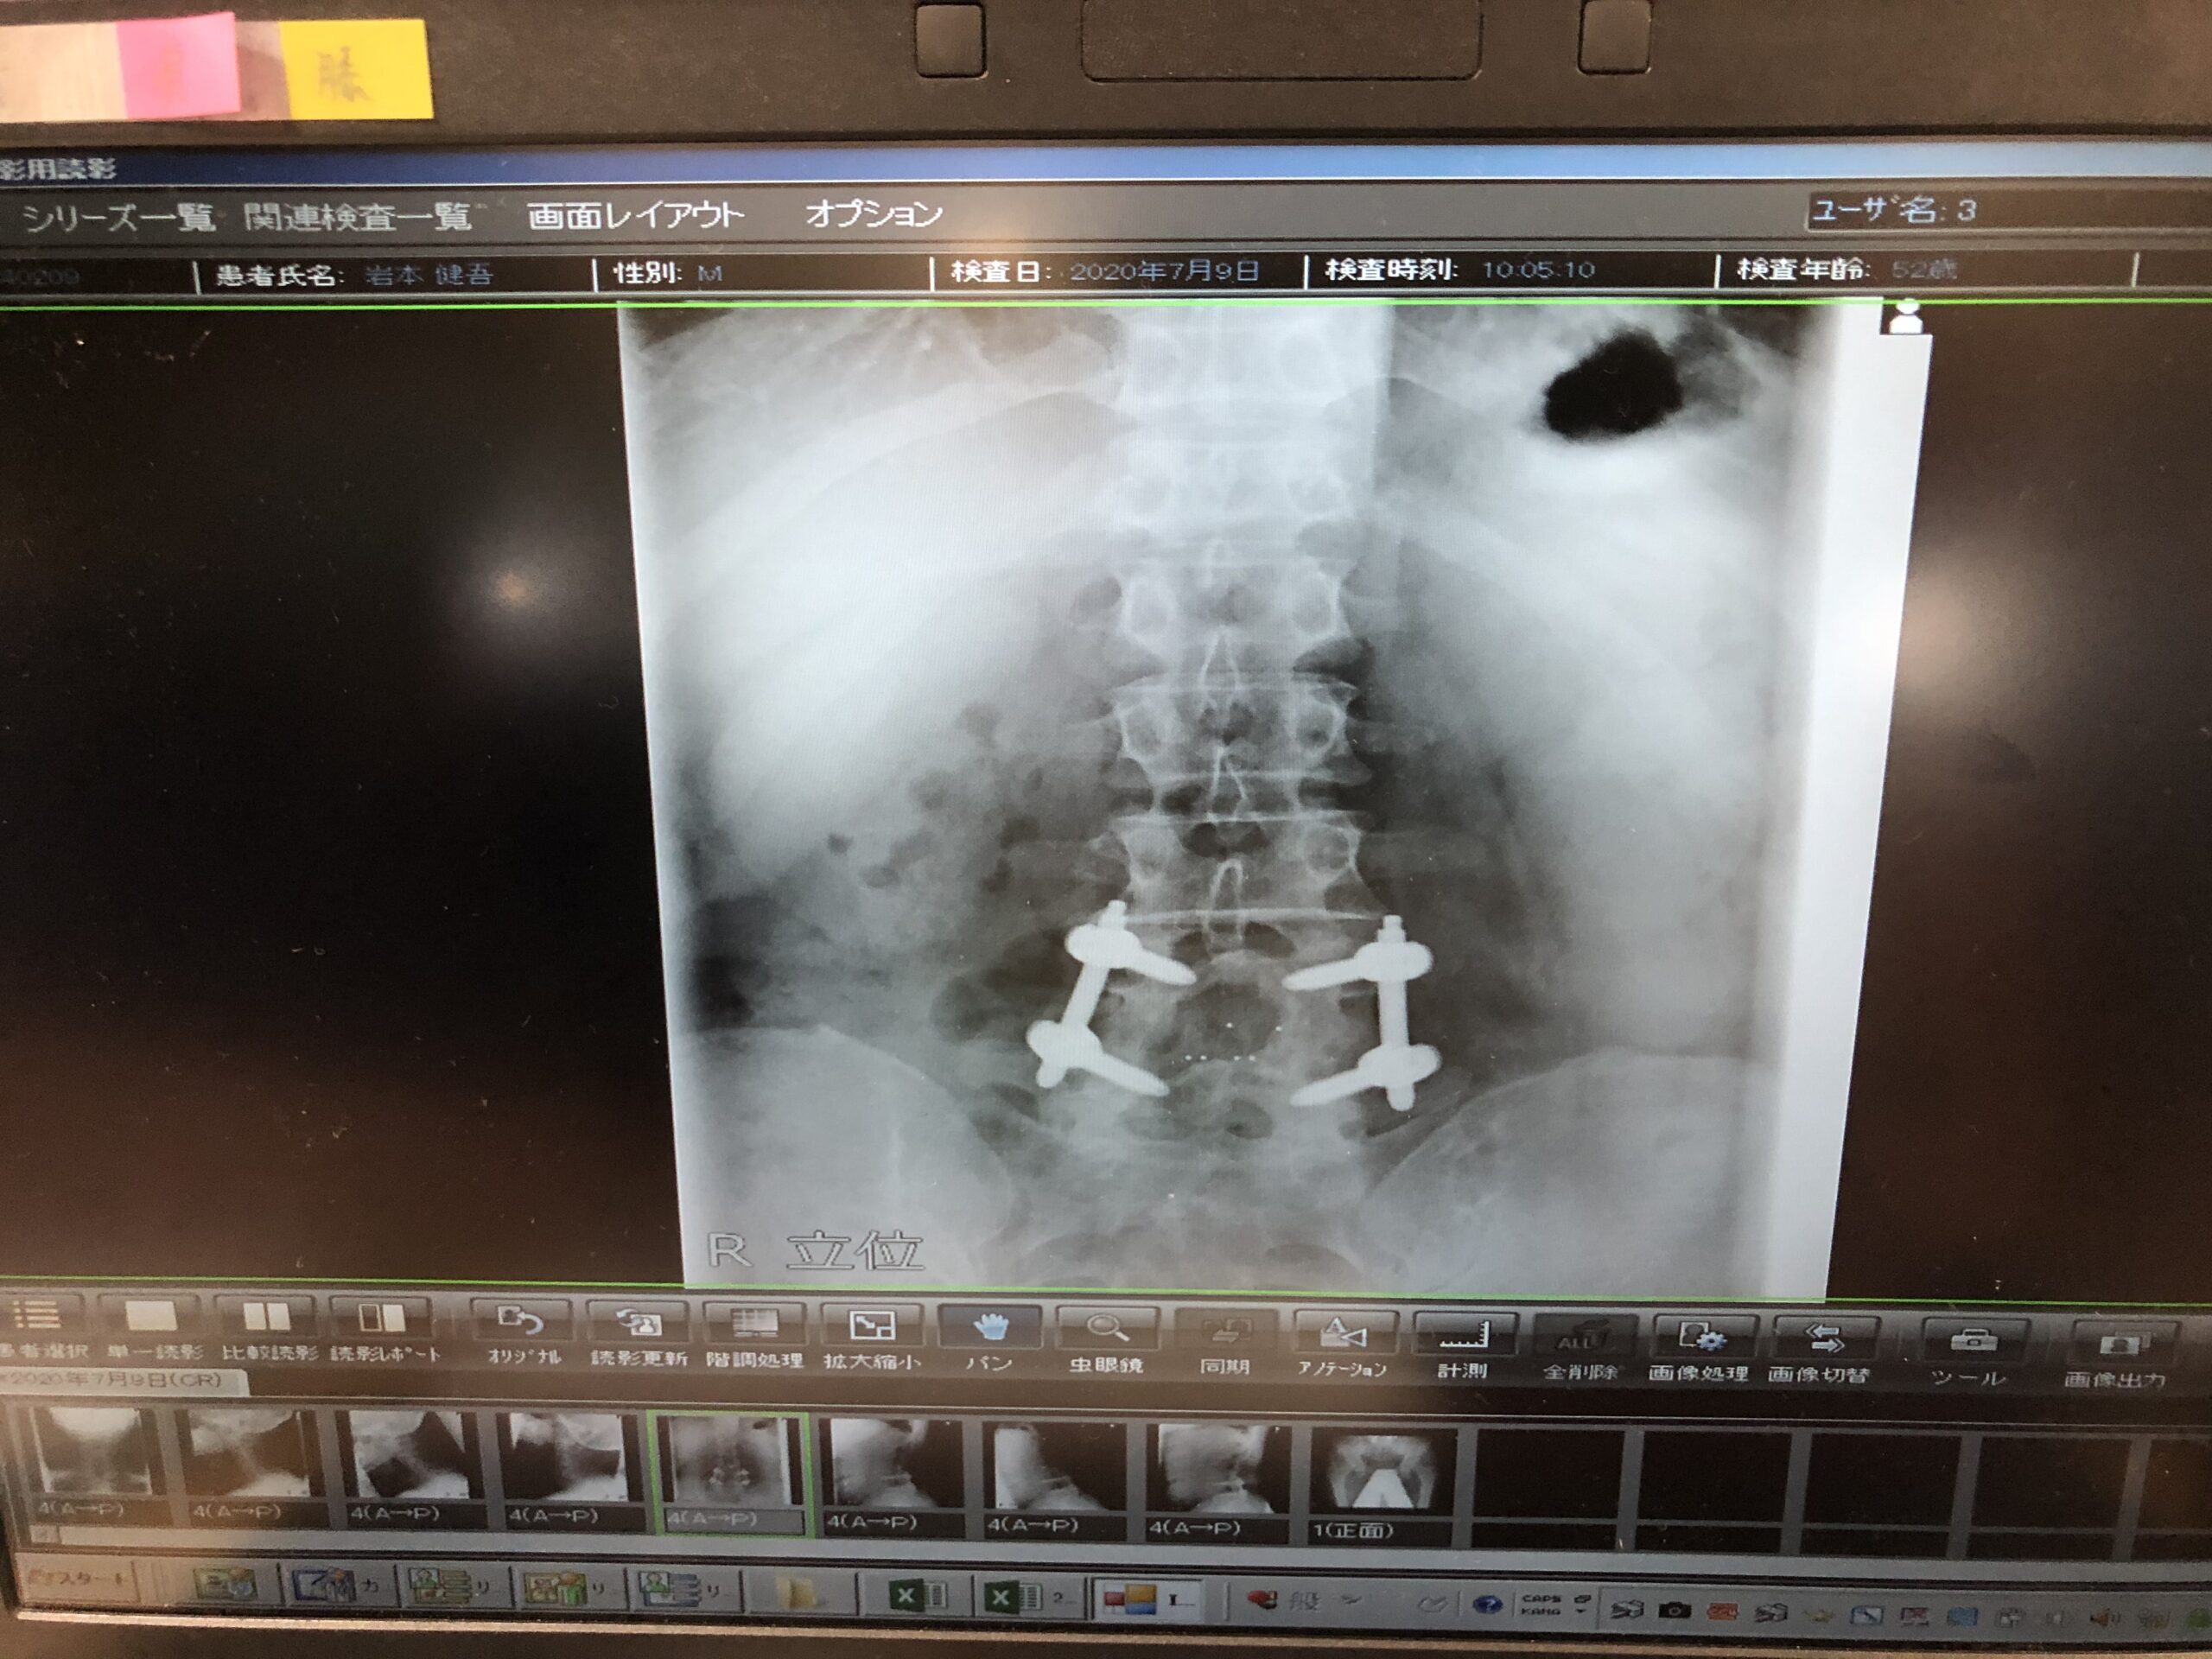

それがこちらの画像です。

一生外れません。

死ぬまでこの状態のまま焼かれます。

焼いた時にこのボトルが残るんでしょうね😖

8時間の手術、輸血も相当なもの。

35針縫って、お尻の軟骨を削って移植。